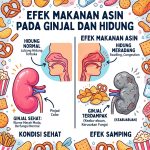

Bahaya Tersembunyi! Efek Makanan Asin terhadap Ginjal dan Hidung yang Sering Diremehkan

infokesehatanhidung.id – Efek makanan asin terhadap ginjal dan hidung ternyata bukan sekadar masalah rasa haus setelah makan. Banyak orang menikmati camilan gurih, makanan instan, hingga lauk tinggi garam tanpa sadar bahwa kebiasaan ini dapat memberi tekanan besar pada tubuh, terutama pada ginjal dan saluran pernapasan bagian atas. Dalam jangka panjang, konsumsi garam berlebihan bisa memicu […]